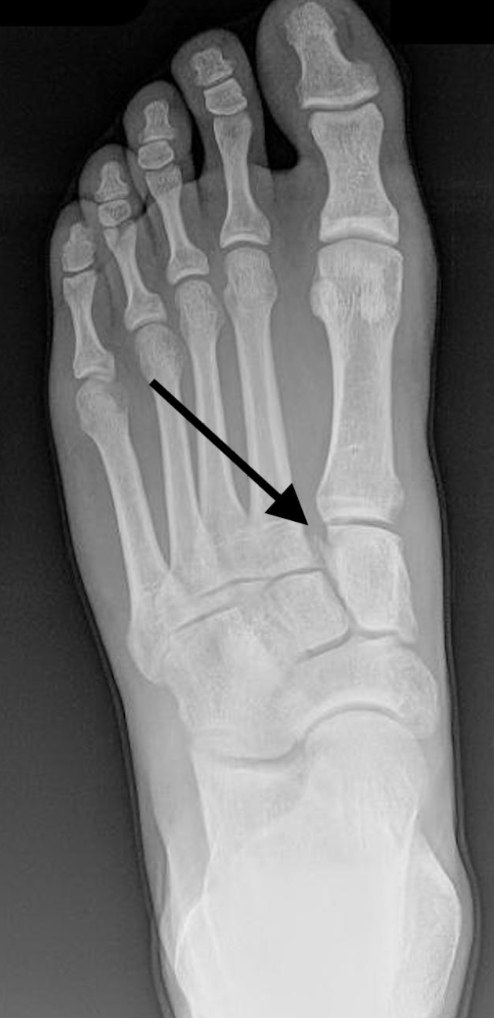

A

A Lisfranc injury is a tarsometatarsal fracture dislocation characterized by traumatic disruption between the articulation of the medial cuneiform and base of the second metatarsal.

* Diagnosis is confirmed by radiographs which may show widening of the interval between the 1st and 2nd ray.